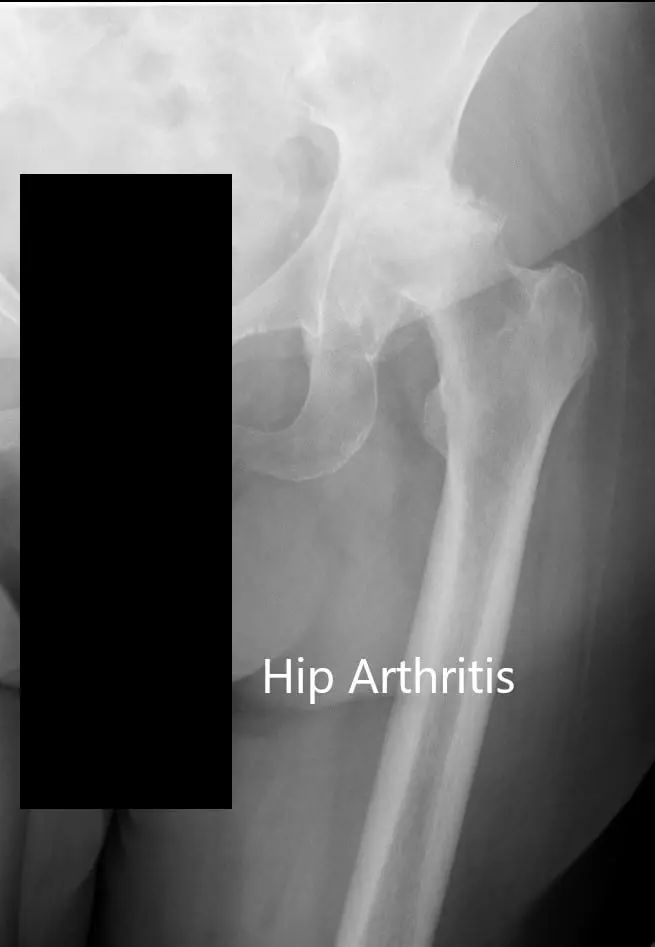

Los estudios de imagen revelaron osteoartritis bilateral de cadera, que era grave en la cadera izquierda con displasia del acetábulo. En vista del dolor de cadera que limita el estilo de vida, le recomendaron una prótesis total de cadera para la izquierda. Se discutieron extensamente con el paciente los riesgos, beneficios y alternativas. El paciente estuvo de acuerdo con el plan.

Radiografía preoperatoria de la cadera izquierda que muestra visión AP y lateral.